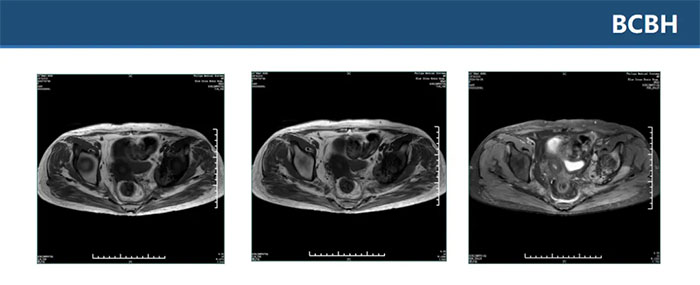

▲ 双侧坐骨、髂骨、骶骨、左侧耻骨多发异常信号伴左髂骨髋臼处骨质破坏,考虑肿瘤性病变,转移瘤待排